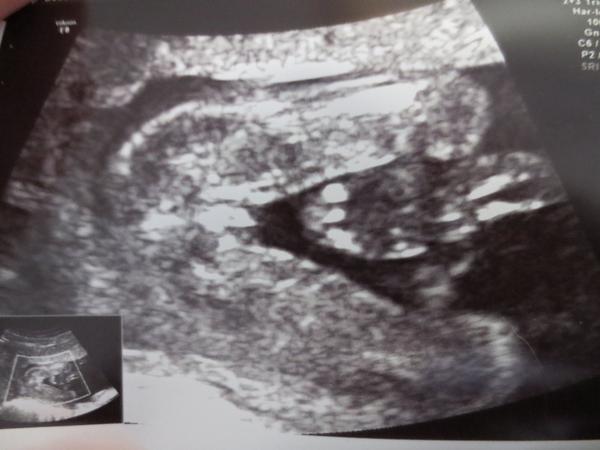

Ahoj maminky a budoucí maminky 😉 Prosím, poradila byste mi některá, co vidíte na fotce z ultrazvuku ve 20. týdnu za pohlaví? Určitě jste foteček viděly už mraky, proto vás žádám o radu...Nechci nikoho ovlivnit, proto svůj tip řeknu později 🙂 Děkuju moc!!!

Osobne se mi to trosku vice zda taky jako holka, ale buh vi, co tam kde vidim 😀

@matahari99 tipla bych holku.